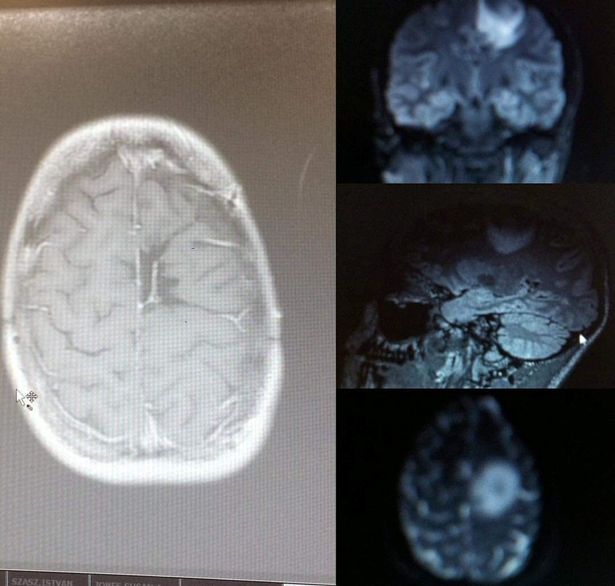

第一次令人费解的事件发生在2013年,在接下来的两年里,艾米又发生了两次癫痫发作,她在健身房昏厥。2015年2月进行的核磁共振扫描发现了肿瘤,最初是良性的。然而,到当年7月,肿瘤已经变成恶性肿瘤,艾米有5%的几率死于肿瘤。

核磁共振扫描发现了一个高尔夫球大小的脑瘤(图片来源:脑肿瘤研究/ SWNS)